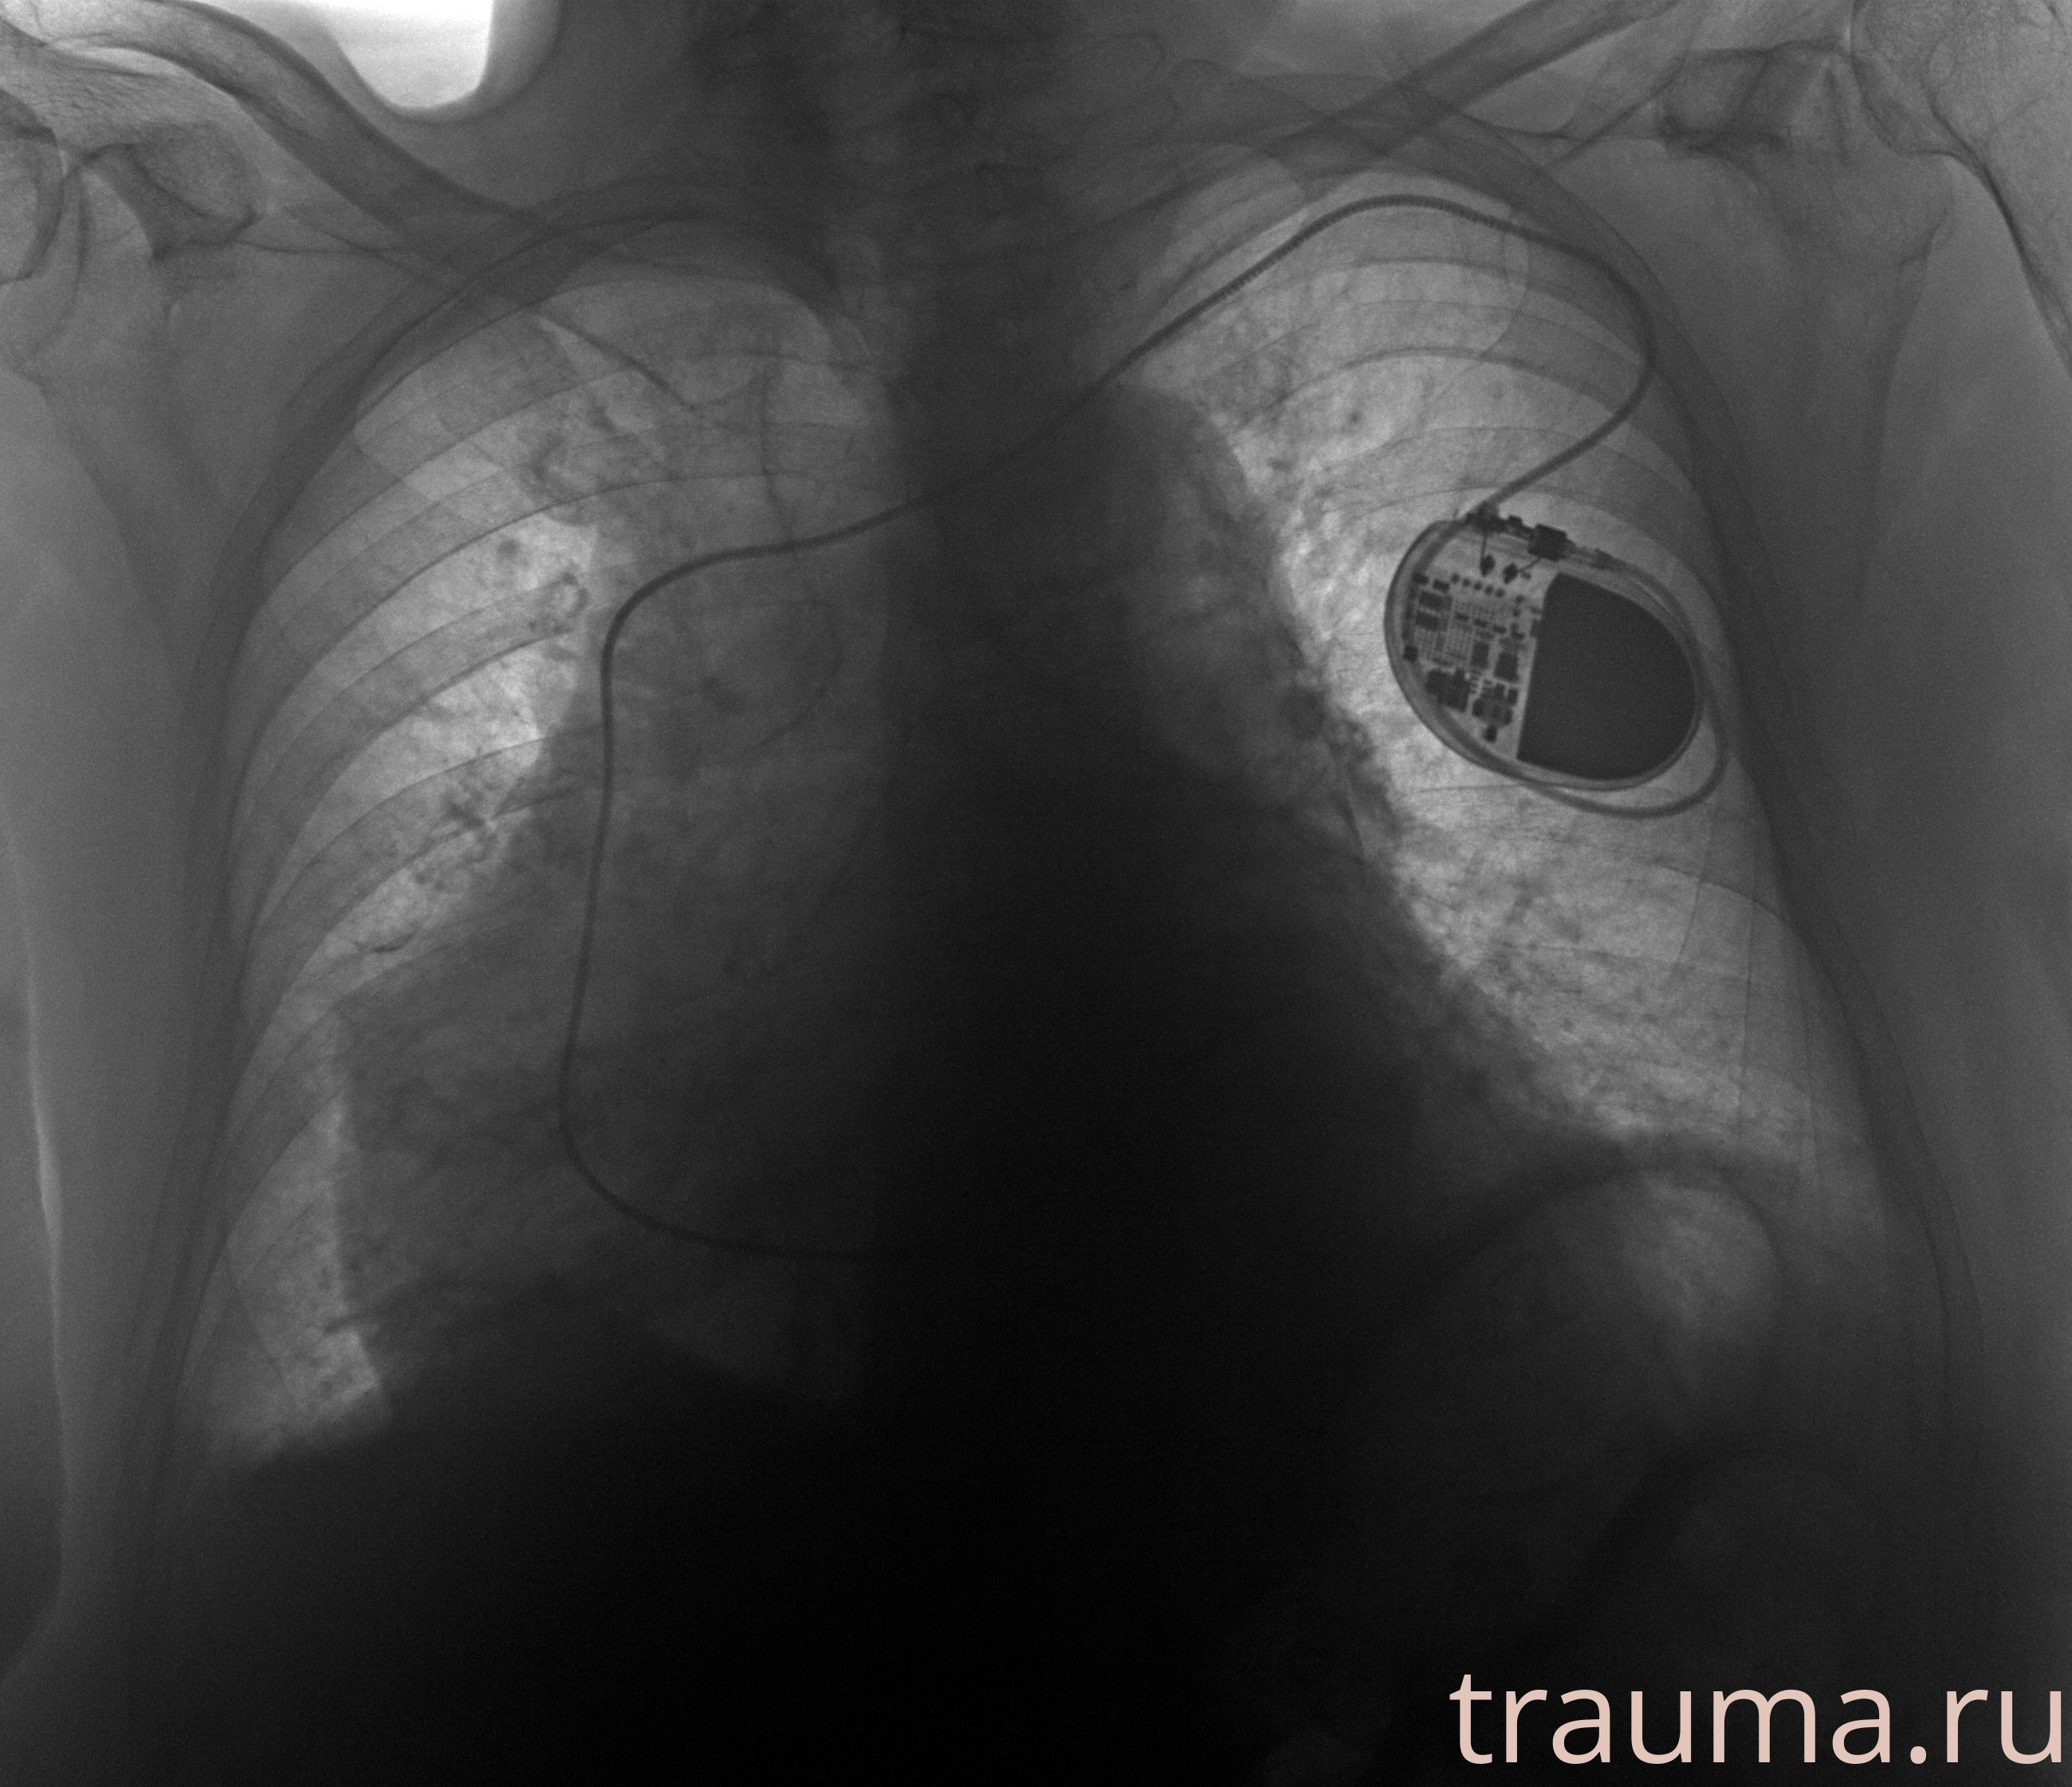

Рентгенограммы

Рентген на дому: по вашему адресу приезжает врач-рентгенолог, травматолог-ортопед с мобильным рентгеновским аппаратом, проводит диагностику травмы или заболевания, делает необходимые рентгенограммы, дает рекомендации по дальнейшему лечению. Получить качественные снимки в домашних условиях возможно благодаря уникальной методике, разработанной МосРентген Центром для института  Склифосовского